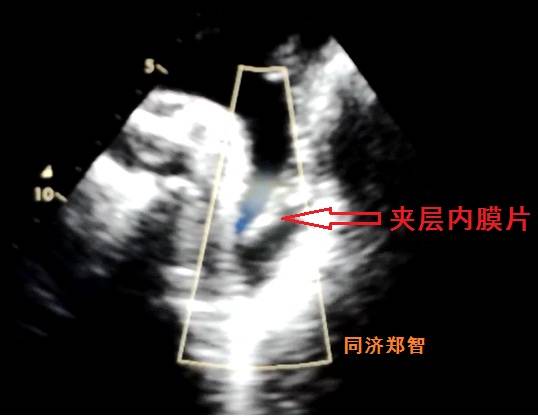

病例八

有时在彩超中也可以视察到内膜片,但其准确性不高,存在假阴性和假阳性的可能。